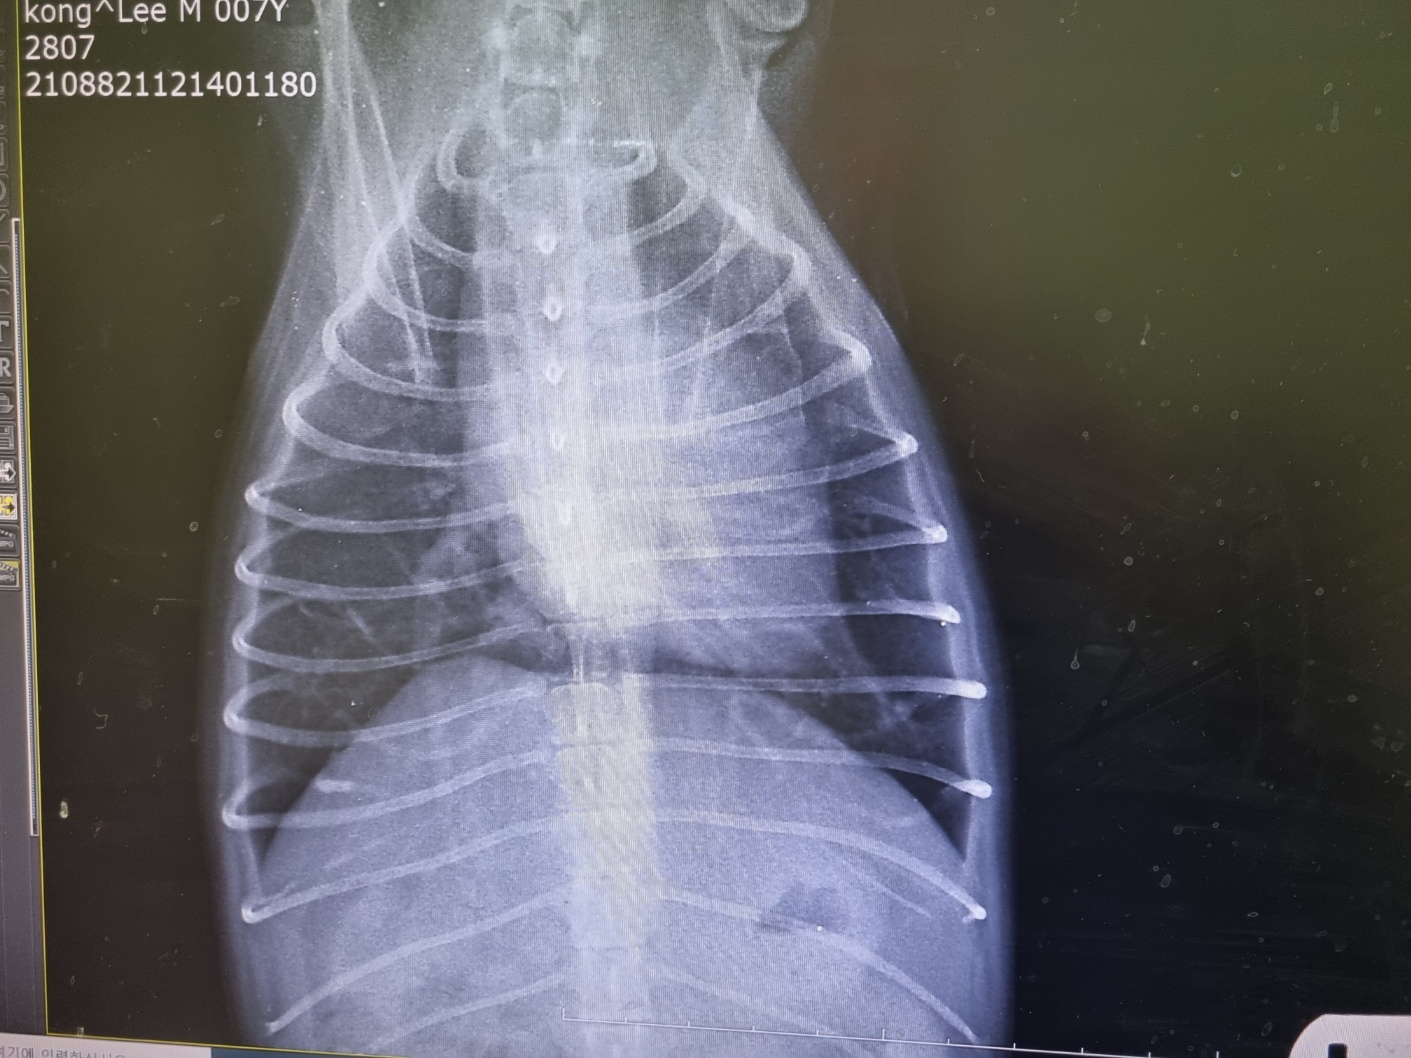

◈ 강아지 호흡기 질병

강아지의 호흡기 질병에는 폐렴, 기관지염, 심장병 등이 있습니다.

이러한 질병은 강아지의 호흡이 가쁘거나 호흡 소리가 이상할 때 의심할 수 있어요.

폐렴의 경우 기침, 콧물, 발열 등의 증상이 나타나며,

기관지염은 기침과 콧물이 특징적입니다.

. 심장병은 운동 시 호흡 곤란이 나타날 수 있습니다.

이러한 증상이 있다면 신속히 수의사의 진찰을 받아야 합니다.